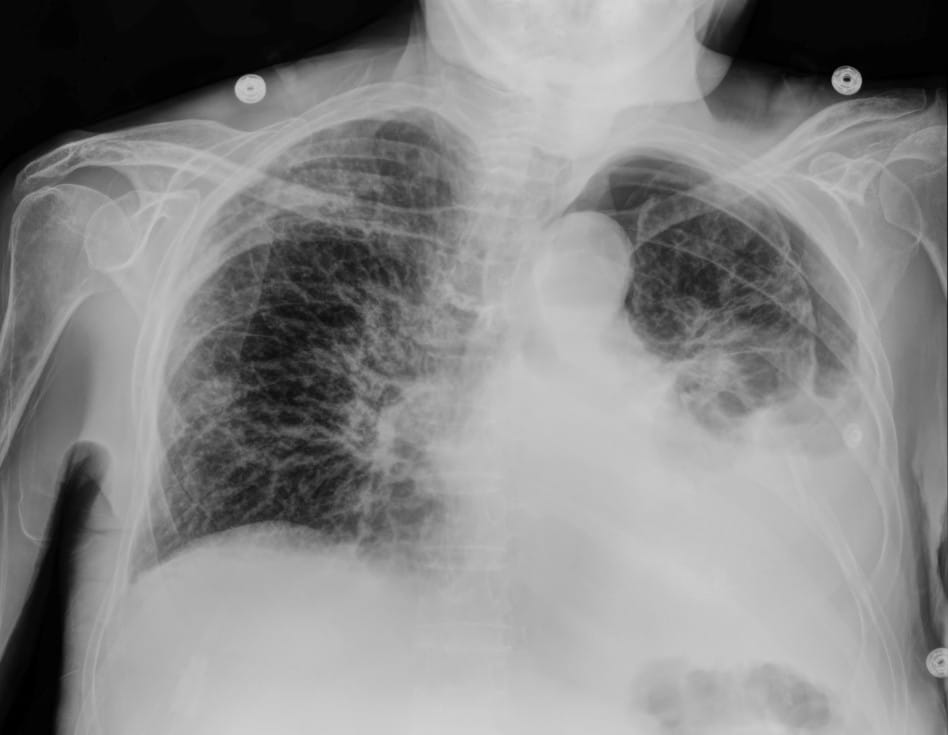

In this case, the conventional DR image shows subtle findings. The spectral soft-tissue image reduces overlying bone, making the pneumothorax more conspicuous. The corresponding bone-selective image highlights a rib fracture, a potential underlying cause of the pneumothorax.

- a conventional digital radiography image

- a bone image

- a soft-tissue image